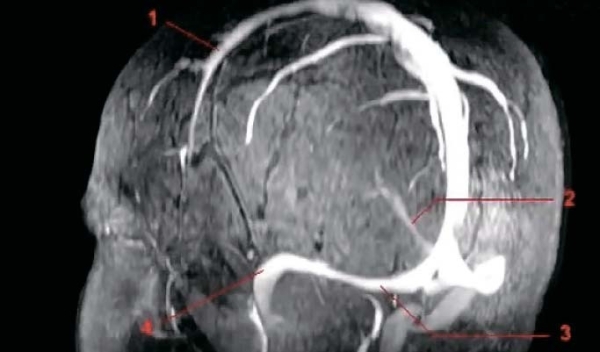

Магнитно-резонансная венография (аппараты МРТ имеют специальную программу для такого исследования). Исследуются синусы головного мозга, а также вены шеи. Всегда сравниваются правая и левая стороны (см. рис. 4, 5).

Рисунок 4. Рентгенограмма синусов головного мозга в норме. 1 — верхний сагиттальный синус, 2 — нижний сагиттальный синус, 3 — поперечный синус, 4 — сигмовидный синус.